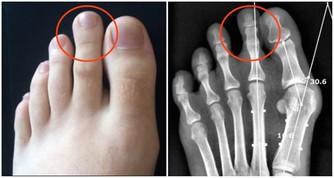

最重要的就是調節飲食習慣,有一些食物能夠導致腎結石的發生,常見的有動物內臟,海鮮、酒精、菠菜、芒果、堅果等,既往患過腎結石的病人對上述食物應該特別小心。